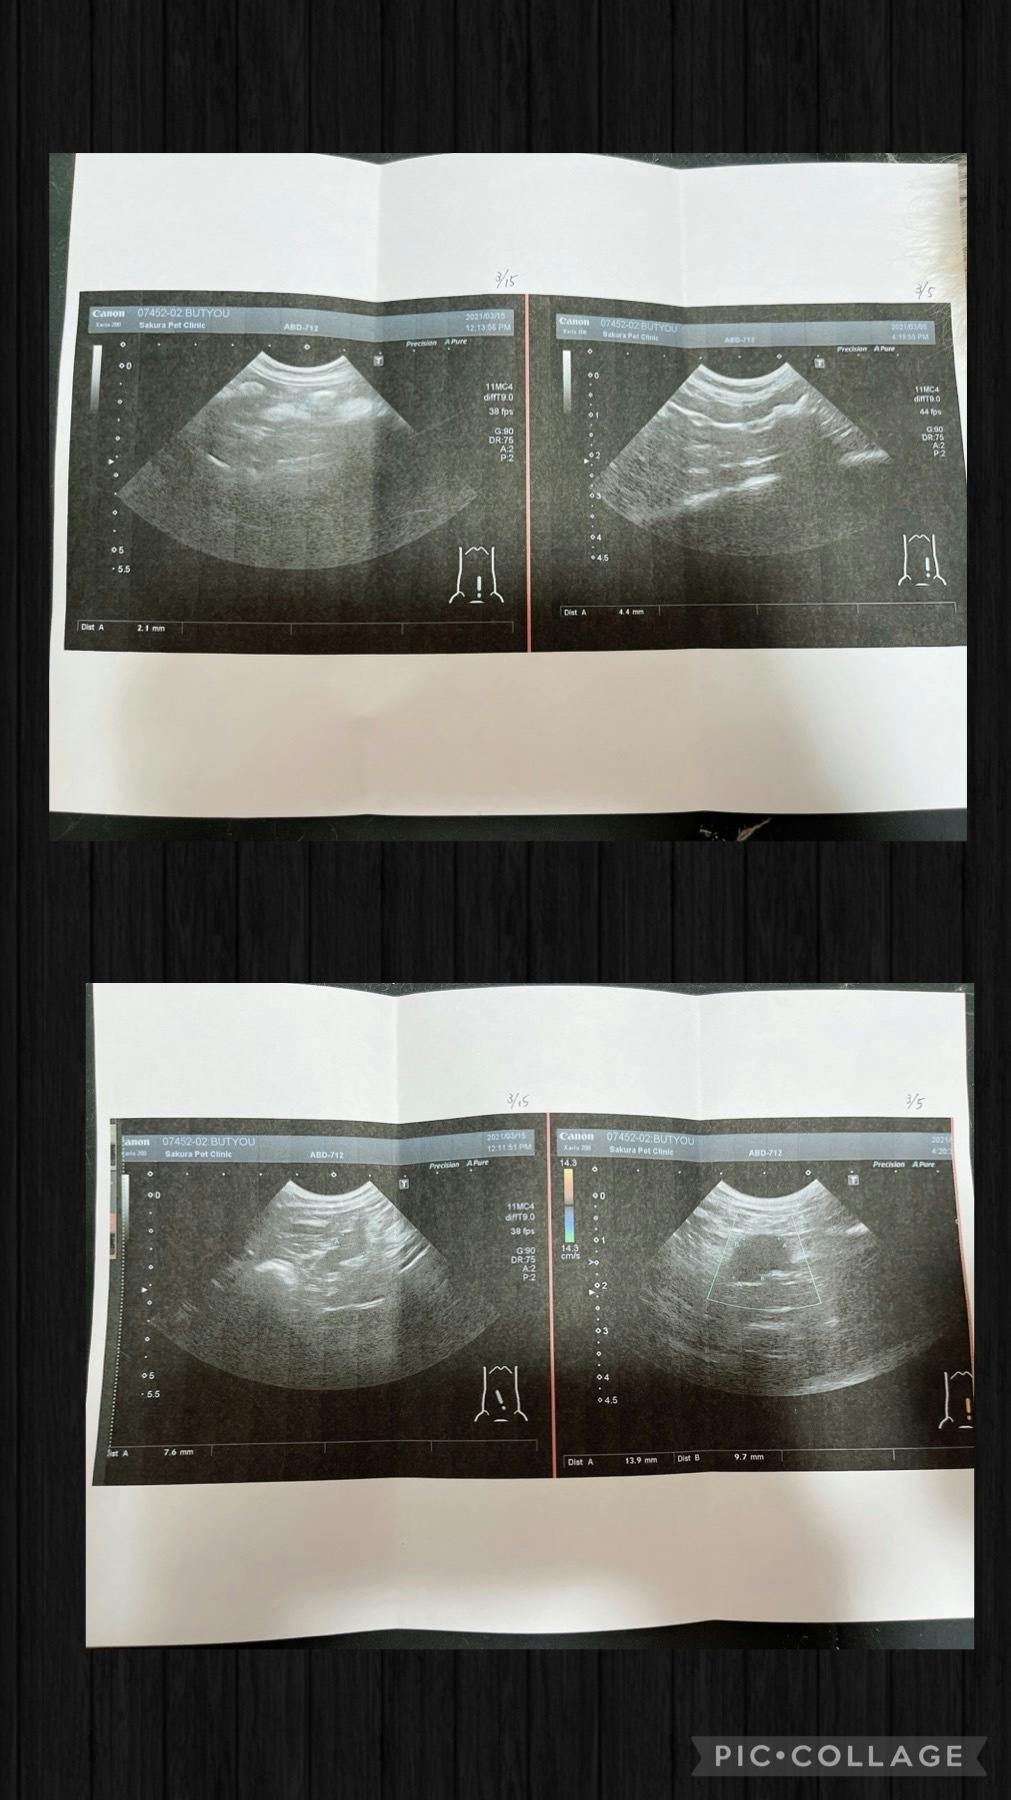

今出来る検査を全てしてもらうと

腸が二倍に腫れて肉芽腫がある

炎症がとても強過ぎる

先生からもFIPドライタイプ初期の疑いが高い

3月15日ありすちゃんと部長の検診に行きました。

ありすちゃんは検査をし無事に寛解となりましたが

部長ちゃんは検査結果FIPドライタイプが確定し